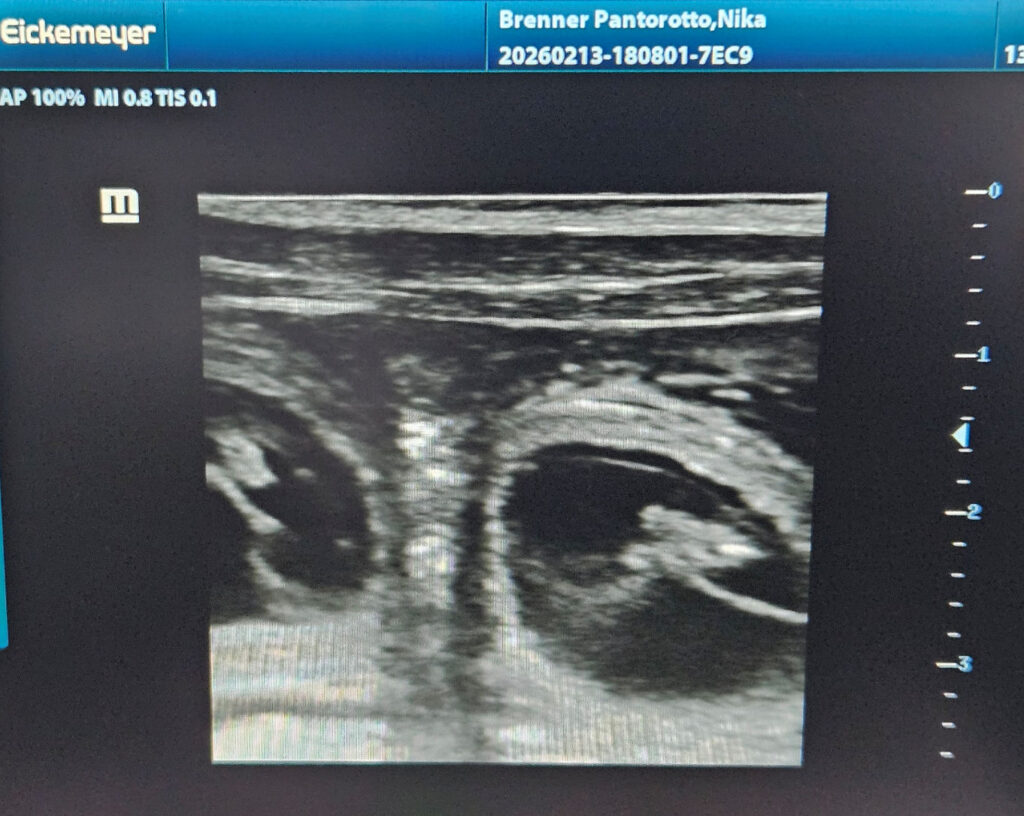

Heute konnten wir im Ultraschall bereits die kleine Q-linge beobachten. Ich dachte es wäre zu früh, denn es ist erst der 25. Trächtigkeitstag. Normalerweise lasse ich immer zwischen dem 28. und 30. Trächtigkeitstag nachschauen, ob meine Hündinnen trächtig sind, da wir aber die kommende Woche beim Tanzfestival in Rust sind musste ich es heute schon machen lassen.